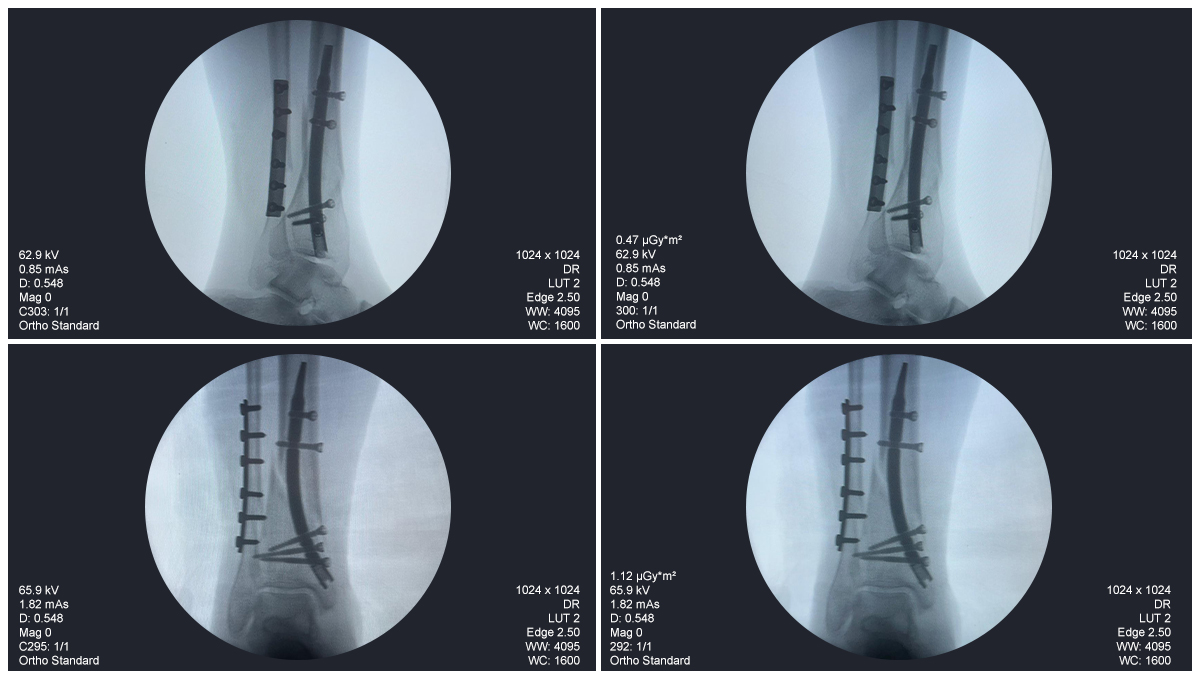

Distal Tibial Nail Fixation Case Study with Fibular Plate Support

Patient:

31-year-old patient

Surgical Area:

Distal tibia and fibula

Product Used:

Distal Tibial Nail

Fibular Locking Plate

Imaging:

Intraoperative C-arm fluoroscopy, AP and lateral views

Case Summary:

This case involved distal tibial fixation using an intramedullary distal tibial nail. Intraoperative fluoroscopy confirmed the position of the nail, distal locking screws, and fibular plate fixatio